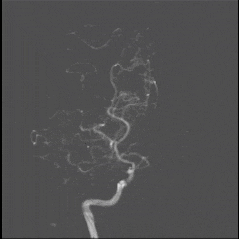

DSA

8月25日.gif

术前诊断:右侧颈内动脉闭塞;高血压病3级 极高危;持续性心房颤动;2型糖尿病;心脏瓣膜置换术后;肥厚型心肌病;肾功能不全;心功能不全。